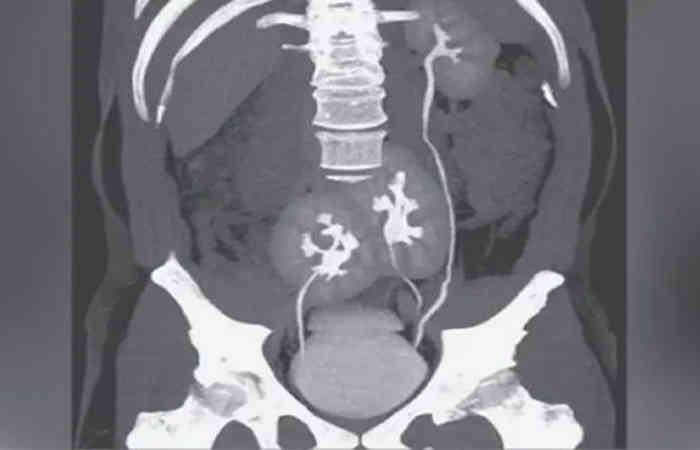

ब्राजील में एक अजीबोगरीब मामला सामने आया है। 6 साल के एक व्यक्ति को पीठ में दर्द था। डॉक्टरों ने सीटी स्कैन किया और पाया कि उसके शरीर में तीन गुर्दे हैं। इतना ही नहीं, तीनों गुर्दे एक ही तरह से काम कर रहे हैं। इस दुर्लभ मामले से डॉक्टरों को भी सकते में ले लिया गया।

डॉक्टरों ने नोट किया कि उन्हें किडनी की कोई अन्य समस्या नहीं है। तीन किडनी होने के बावजूद, तीनों किडनी का आकार भी सामान्य है। आमतौर पर ऐसे मामलों में एक किडनी काम नहीं करती है। या आकार छोटा या बड़ा हो सकता है, लेकिन इस युवा के मामले में ऐसा कुछ भी नहीं देखा गया था।

अब तक दुनिया में तीन किडनी के केवल 100 मामले सामने आए हैं। 2016 में इंटरनेट जर्नल ऑफ रेडियोलॉजी में प्रकाशित एक रिपोर्ट के अनुसार, दुनिया में केवल 100 लोग पैदा हुए जिनके शरीर में तीन गुर्दे थे।